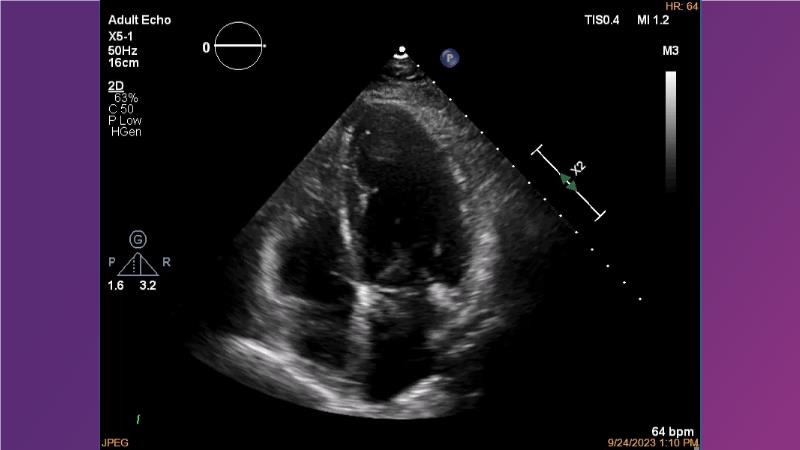

Gain expertise in selecting the appropriate TAVI device for achieving stable deployment in a 90-degree horizontal aorta. Discover techniques for ensuring smooth deliverability, particularly when navigating through tight and tortuous anatomies. Additionally, learn strategies to prepare for future coronary access, irrespective of the height of the left or right coronaries.

• To learn how to select your TAVI device in order to achieve stable deployment in 90 degrees horizontal aorta